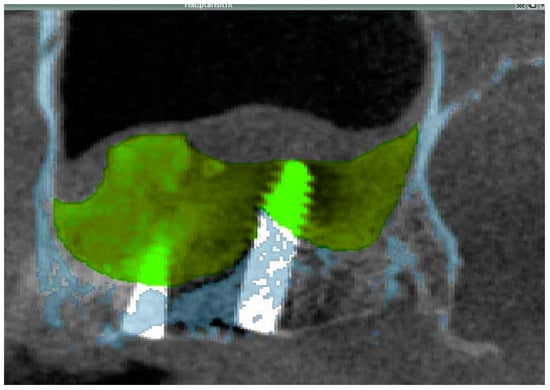

2.3.1. Cone Beam CT

2.3.2. Data Transfer, Analysis and Volume Determination

3.2. Radiological Results